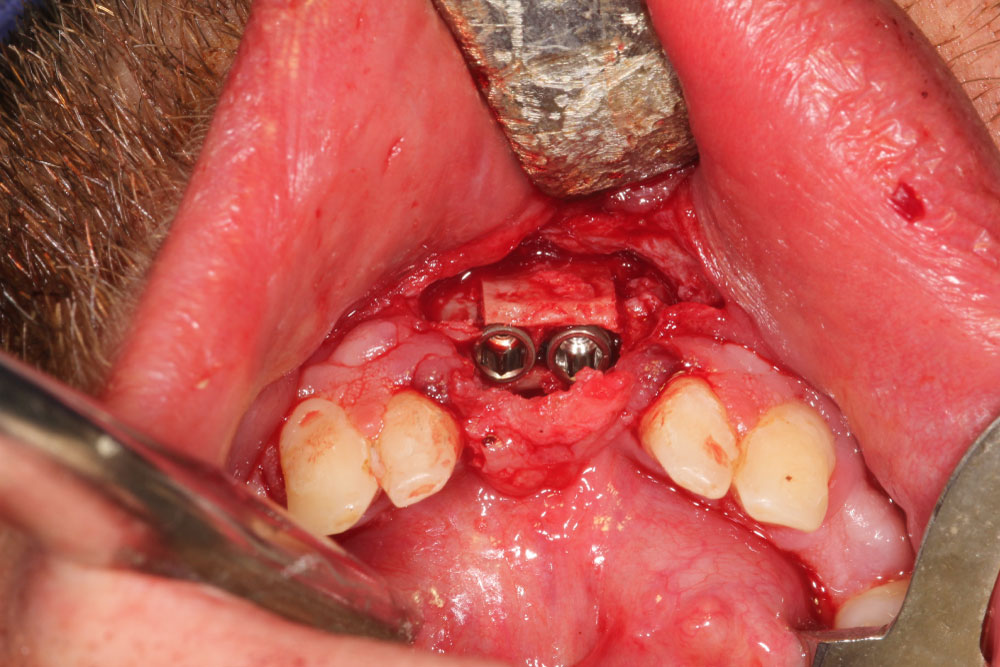

Figure 10: Bone split region 31, 41 and dental implantation 31, 41. View Figure 10

Figure 11: Clinical situation after selected tooth extraction and implantation in region 16, 14, 12, 22, 11, 21, 24, 26. View Figure 11